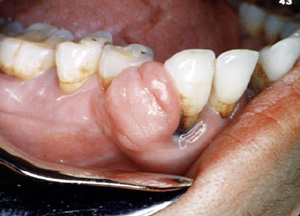

Éste es un ejemplo bastante típico de una lesión  nodular, firme cubierta por  epitelio normal. El color indica que hay proliferación vascular.